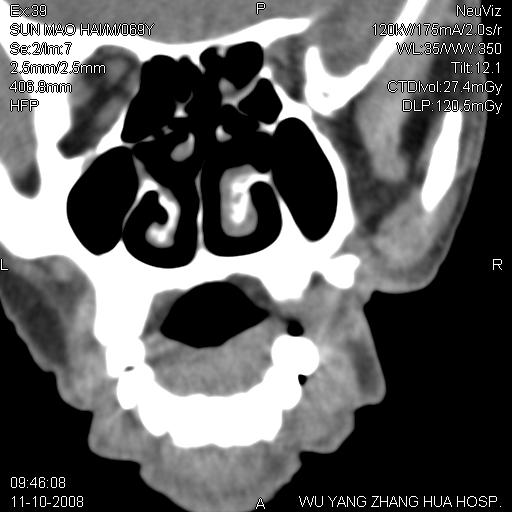

标题: CT16568:右面部瘘管半年余,无其它不适. [打印本页]

标题: CT16568:右面部瘘管半年余,无其它不适.

考虑右上颌异位齿(或斜向阻生齿)并根尖脓肿。

1.右上颌异位齿

2.右上颌化脓性骨髓炎

3.右下鼻甲肥大

支持三楼意见。(这种长法还真少见,再长再尖点就成獠牙了。)